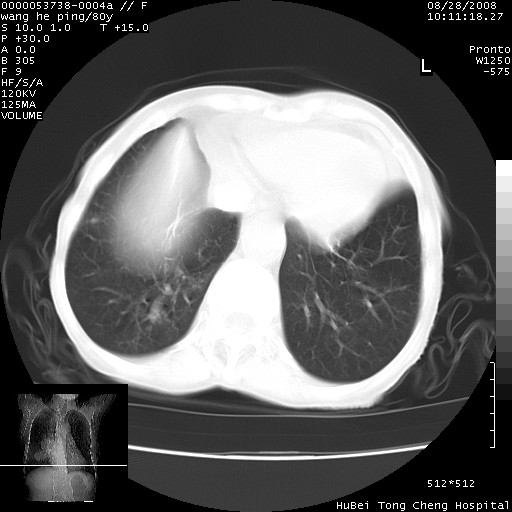

以下是引用黑白光影在2008-8-28 22:33:00的发言:[br]右肺中央型肺癌伴阻塞性肺炎,肺癌肺转移。

以下是引用lshx在2008-8-28 22:06:00的发言:[br]1.右肺中心型肺癌伴阻塞性肺炎,不除外双 肺早期转移。[br]2.心包积液。

以下是引用随光逐影在2008-8-29 7:40:00的发言:[br]1)右肺中心型肺癌伴阻塞性肺炎,肺内转移。2)心包积液(少量)。

以下是引用wqs571018在2008-8-28 21:56:00的发言:[br]右肺中心型肺癌伴阻塞性肺炎可能。

以下是引用liuyue在2008-8-28 22:46:00的发言:[br]1.右肺中心型肺癌伴阻塞性肺炎。[br]2.心包积液(少量)。